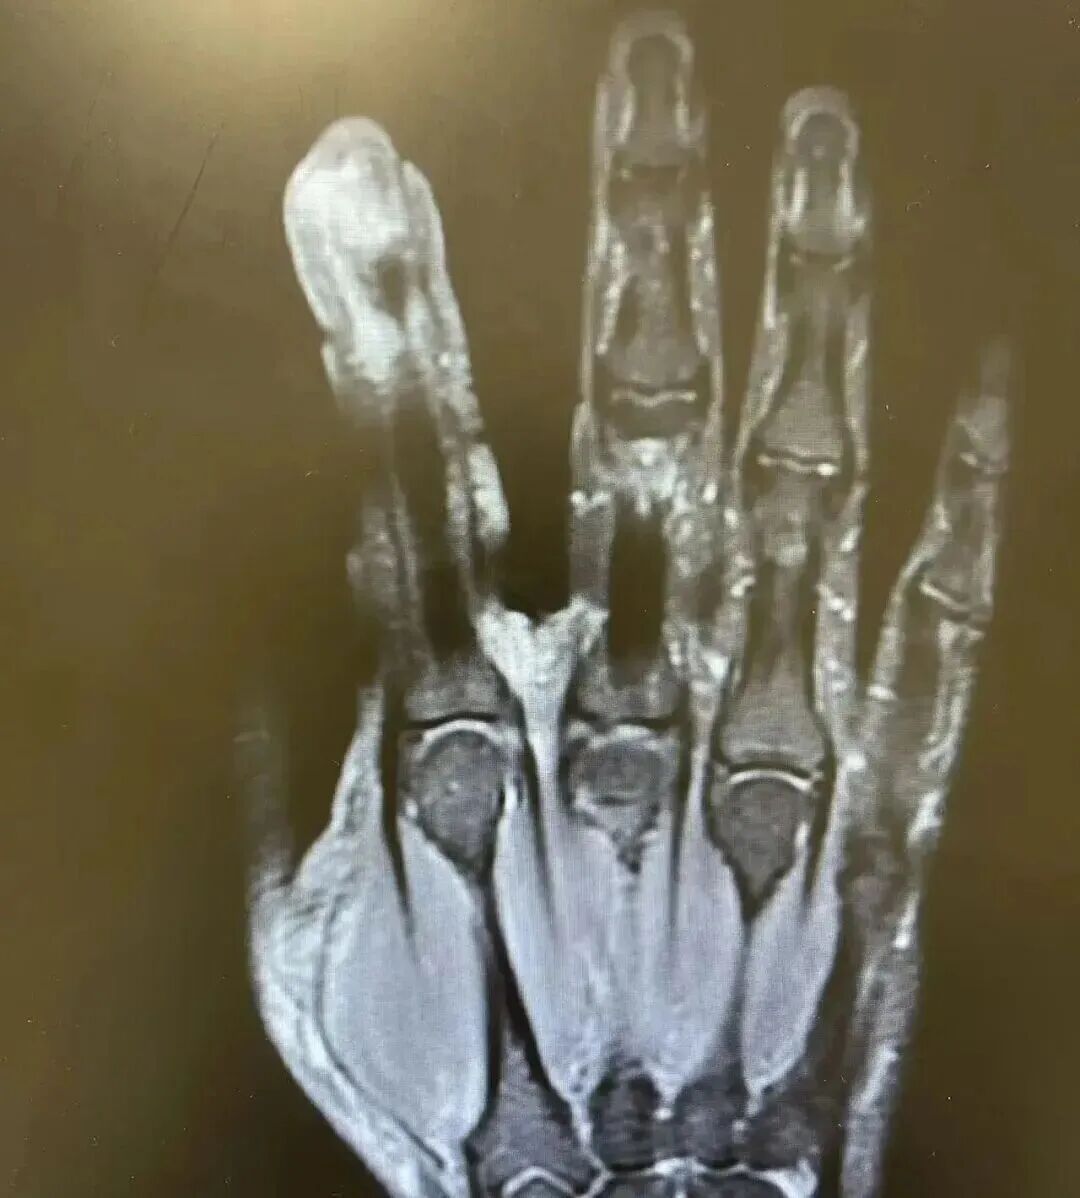

经检查,李大哥破溃的左手指尖严重感染,厌氧消化链球菌顺着破损处钻到骨头里,引发了严重骨髓炎。

医生紧急手术,帮李大哥“刮掉”坏死的骨头碎片,清除了坏死的肌肉与皮肤。医生表示,如果再晚一步,不仅手指保不住,还可能会引起脓毒血症,甚至危及生命。